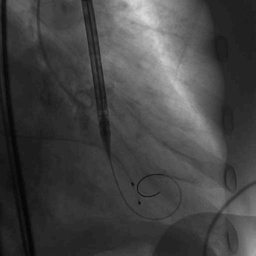

主动脉根部造影

球囊预扩图